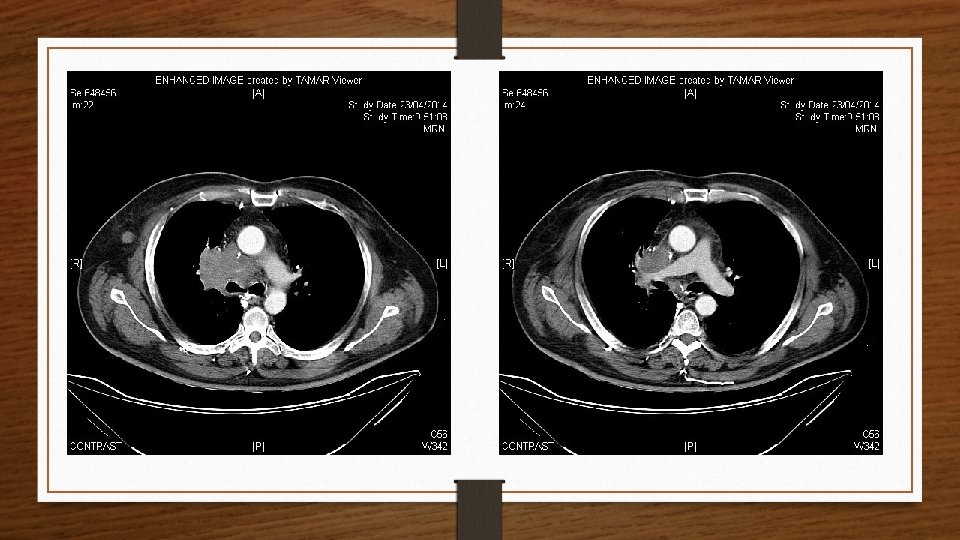

Radiografía de Tórax

RESUMEN • Paciente varón de 60 años fumador • Dolor torácico derecho + disnea + hemoptisis + edema facial/cervical + cambio en el tono de voz • Exploración: edema facial/cervical, hipoventilación CSD + IY • Rx: Masa en LSD (Signo de Golden) • TC Tórax: masa pulmonar LSD que se extiende a mediastino con una cava superior filiforme.

URGENCIA ONCOLÓGICA

Urgencia Oncológica: SVCS • • • Hospitalizar al paciente. Oxigenoterapia Elevación de la cabecera (permite disminuir presión venosa) Furosemida IV (vigilando la deshidratación + iones) Pauta de bolo de corticoides.

El pronóstico se establece más por el tipo histológico causante que por el desarrollo del SVCS en sí mismo, lo que refuerza la importancia de llegar a un diagnóstico etiológico correcto. 75 -85% Carcinomas de Células Pequeñas. Segundo lugar: Carcinomas epidermoides.

Broncofibroscopia AP: carcinoma no célula pequeña compatible con carcinoma epidermoide.